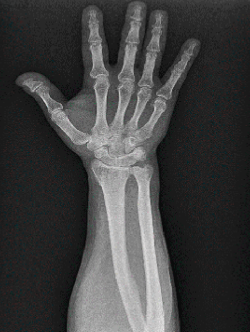

Se solicitan estudios de imagen. En primer lugar, rayos X de muñeca en proyección anteroposterior (AP) (Figura 1), en los que se evidencia un aumento del espacio cubital y presencia de la fusión lunopiramidal. Se coloca una inmovilización con muñequera elástica. Se solicita (Figura 2) tomografía axial computarizada (TAC) para la confirmación del diagnóstico y resonancia magnética (RM) (Figura 3) de mano para valorar las estructuras blandas. Los hallazgos de la TAC reportan la coalición lunopiramidal de tipo Minnaar III y la RM realizada para valorar lesiones asociadas de partes blandas reporta sinovitis. El resto de los elementos no muestran alteraciones.

Figura 2. Imagen de tomografía computarizada multicorte (TCM) que muestra reconstrucción multiplanar (MPR) en el plano coronal, evidenciándose la coalición (Minnaar de tipo III).